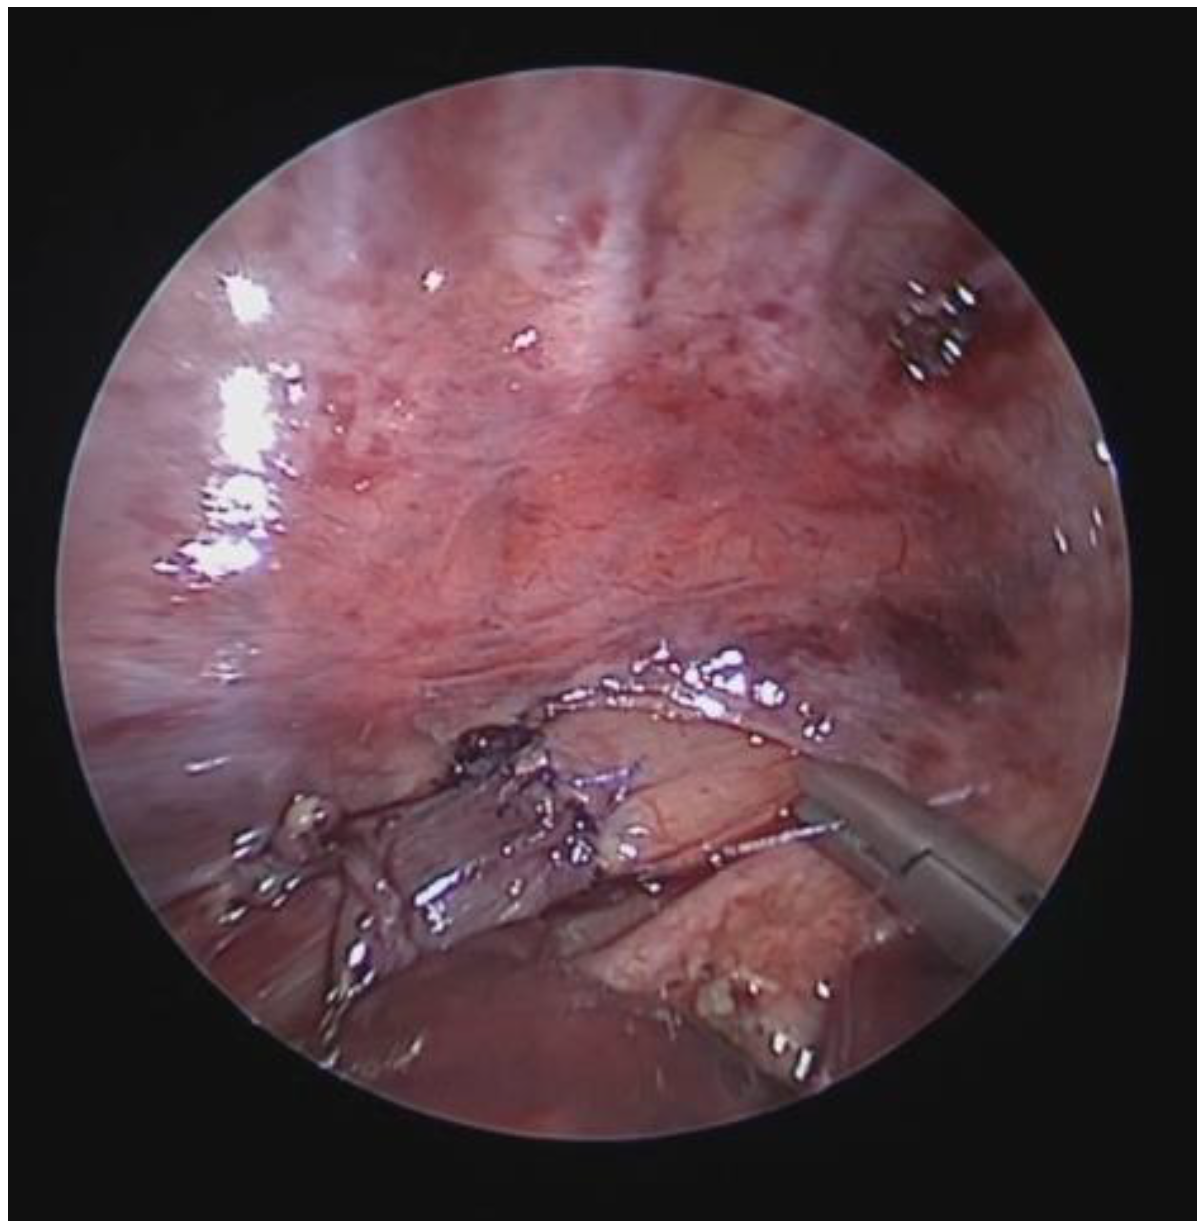

- Dynamic VBS (DVBS), in which the patient (while sedation, as it is at the end of the examination, becomes increasingly superficial), is stimulated to cough by contact of the endoscope with the carina and/or main bronchial walls. The patient, performing abdominal straining to attempt to cough, increases the intrathoracic pressure similarly to what happens when the patient is awake. The increasing pressure, if there is malacia/extrinsic compression or hypermobility of the pars membranacea, causes a pathological (i.e., greater than 50%) decrease in tracheal lumen, as can happen in everyday life [27,28].

4.4. Posterior Tracheopexy (PT)